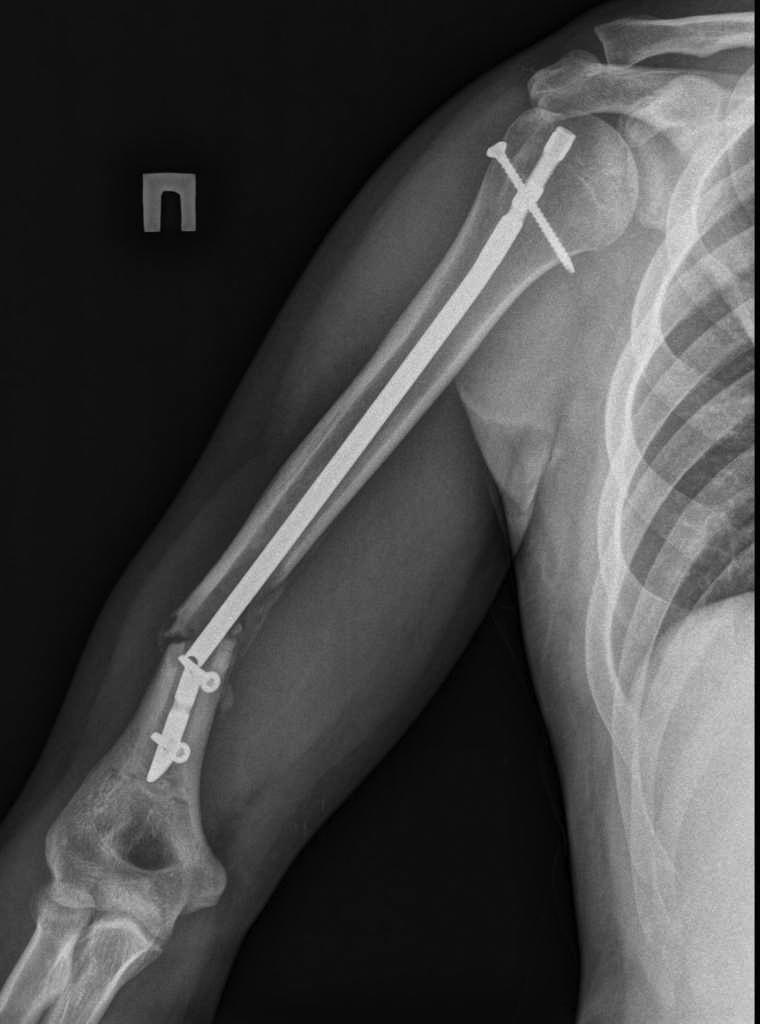

Перелом штифта

Пациент 25 лет, в сентябре 2012 г ДТП. Кроме всего прочего, открытый перелом правого плеча с дефектом костной ткани. При поступлении выполнено ПХО и ЧКО из 2 колец. После заживления раны выполнен БИОС плеча. Штифт сОлидный, Остеомед. Пару дней назад во время попытки открытия крышки банки (нагрузка по ротации) почувствовал боль в плече. Результат на снимке. Планируем удалить оба отломка (дистальный открыто) и перештифтовать более массивным штифтом. Вопрос №1: есть ли вариант в данном случае закрыто удалить дистальный франгмент НЕканюлированного штифта. Особых инструментов для удаления сломаных штифтов не имеем. Вопрос №2: как вариант рассматриваем выполнить ЧКО удалив предварительно только проксимальный фрагмент штифта. СтОит ли? Вариант накостного остеосинтеза с пластикой и без не рассматриваем. Спасибо за внимание.